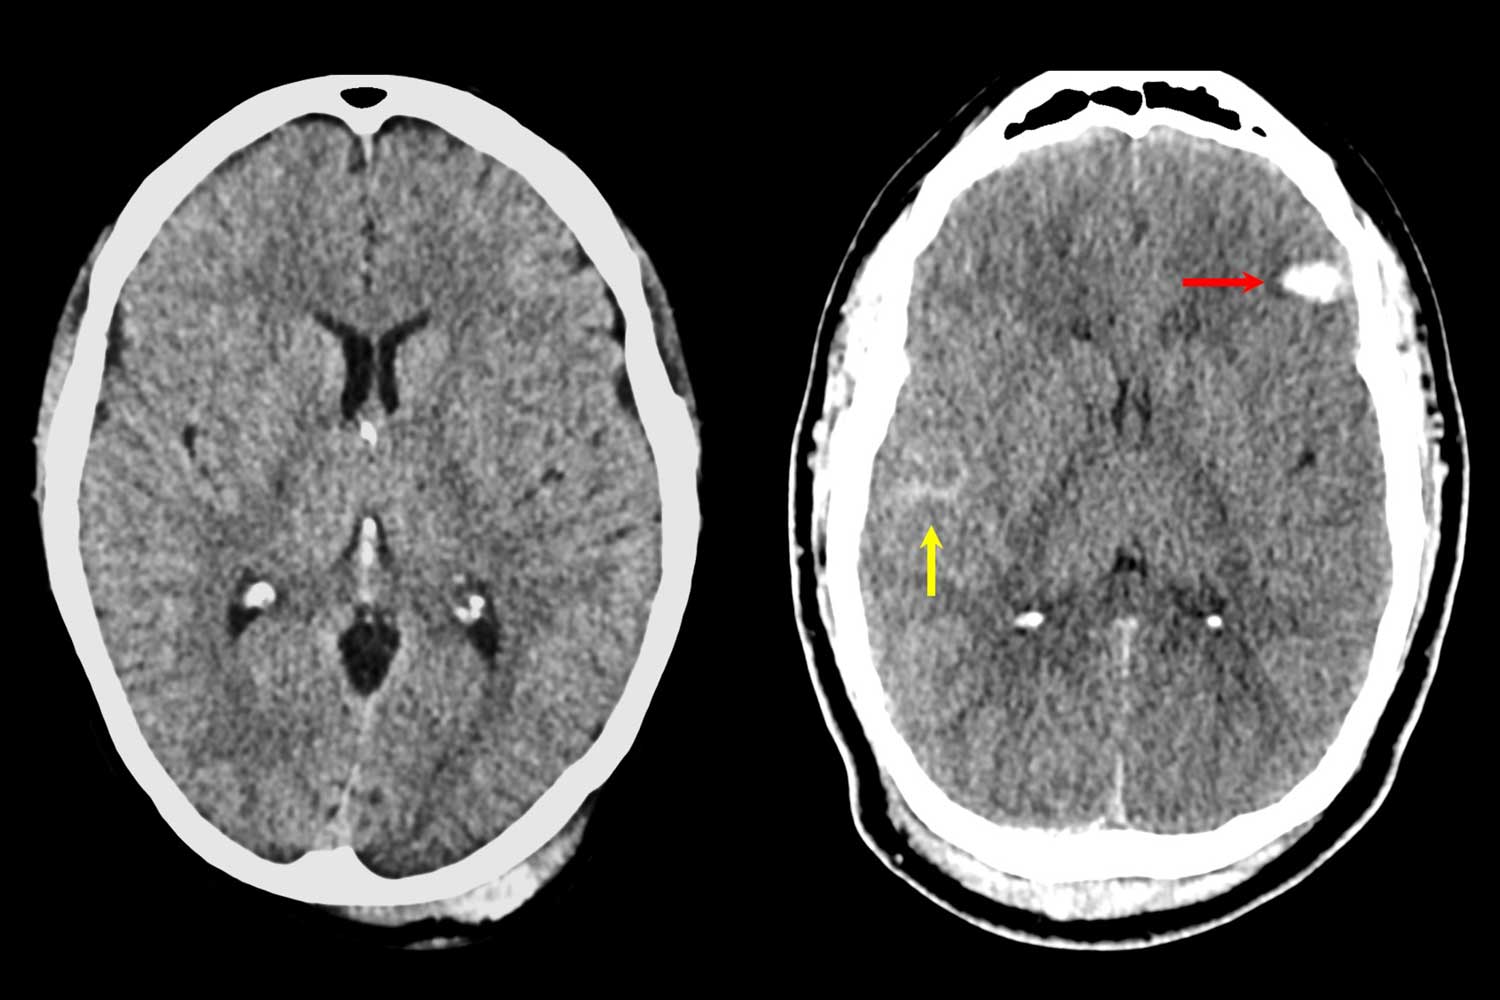

These images show how treatment is impacted by the new TBI framework. The left image shows a clear CT, but a higher biomarker level and a brief period of amnesia and other symptoms would result in follow-up and symptom-targeted treatment.